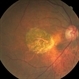

- optical coherence tomography (OCT), fundus autofluorescence (FAF), geographic atrophy, enhanced depth imaging, foveal sparing

- This is a combined FAF/SD-OCT in EDI mode of a patient with geographic atrophy and foveal sparing.